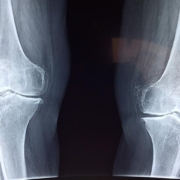

Healthy joints are crucial for an active and pain-free life. Everything from walking and running to simply picking up a pen relies on the smooth operation of our musculoskeletal system. But what we eat plays a surprisingly large role in joint health. The right foods can help reduce inflammation, strengthen cartilage, and even ease arthritis pain. this article explores the power of joint-friendly foods and how incorporating them into your diet can support your musculoskeletal health from the inside out.

Inflammation is a common culprit in many joint problems, including osteoarthritis. Certain foods can either increase or decrease inflammation in the body. By choosing foods known for their anti-inflammatory properties, you can definitely help protect your joints and reduce pain.Other nutrients, like Vitamin D and Calcium, are essential for strong bones, which in turn support healthy joints.